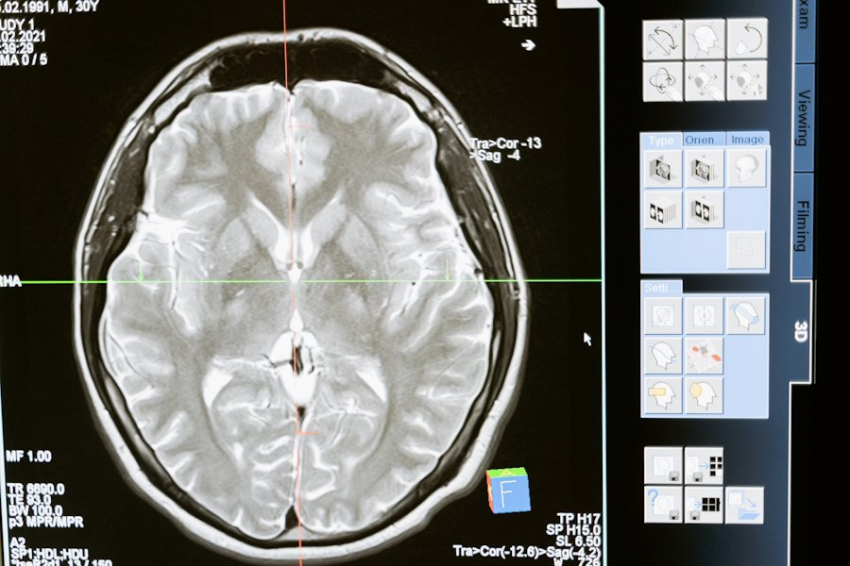

Специалисты обратили внимание на область мозга, отвечающую за настроение и тревогу, а также на уровень серотонина. Их исследования показали, что сильный испуг переключает выработку глутамата на гамма-аминомасляную кислоту (ГАМК), что подавляет нейронную активность.